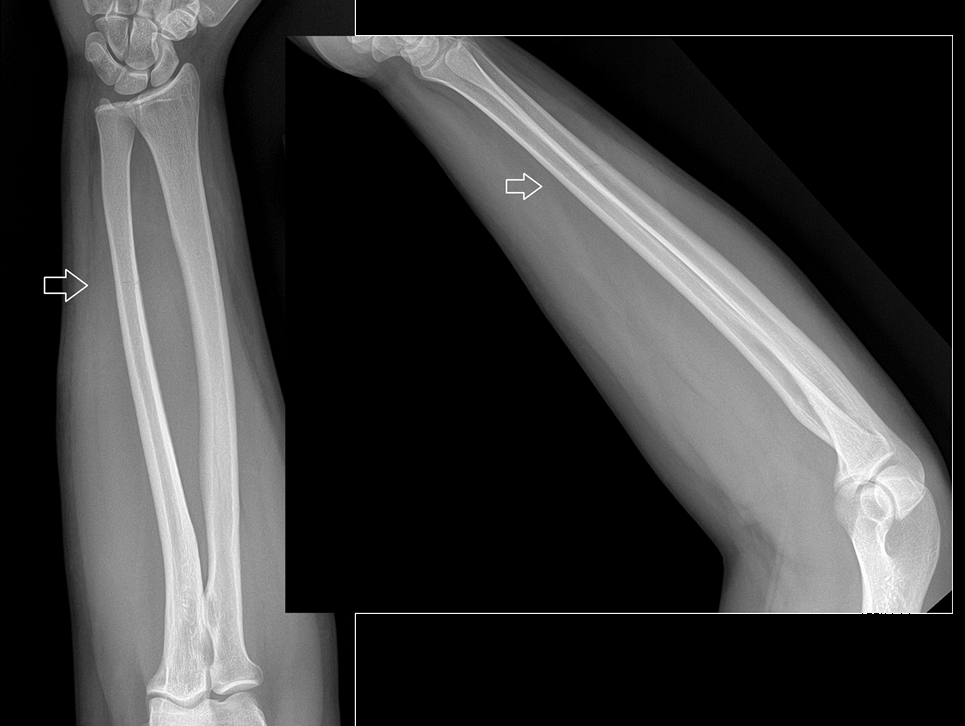

An 80 year old female presents to your office with a left ring finger deformity after a fall one week ago. She initially went to urgent care and xrays were unremarkable for a fracture (Figures 1 and 2). A photo of her left ring finger is shown in figure 3. On physical exam the left ring finger is in hyperextension at the PIP joint and flexion at the DIP joint. She able to flex her PIP joint with full motion. What is the best treatment option?